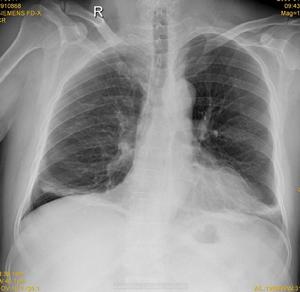

1.放射學檢查 放射學檢查是診斷肺不張最重要的手段。常規胸部平片通常即可明確葉或段不張的存在及其部位。肺不張的放射學表現變化較大常常是不典型的。在投照條件不夠的前後位或後前位攝片,由於心臟的掩蓋,左下葉不張常易漏診。上葉不張可誤認為縱隔增寬,包裹性積液亦與肺不張相似,且大量胸腔積液可掩蓋下葉不張。支氣管空氣征可排除完全性支氣管阻塞,但不能除開肺葉萎陷。

1.放射學檢查 放射學檢查是診斷肺不張最重要的手段。常規胸部平片通常即可明確葉或段不張的存在及其部位。肺不張的放射學表現變化較大,常常是不典型的。在投照條件不夠的前後位或後前位攝片,由於心臟的掩蓋,左下葉不張常易漏診。上葉不張可誤認為縱隔增寬,包裹性積液亦與肺不張相似,且大量胸腔積液可掩蓋下葉不張支氣管空氣征可排除完全性支氣管阻塞,但不能除開肺葉萎陷。